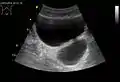

- Divertículo de la vejiga urinaria de un hombre de 59 años, plano transversal